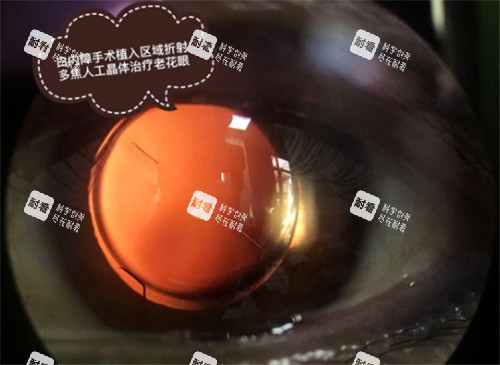

再者是人工晶体的费用。

这是整个费用中变数较大、也是差价较显著的部分。

人工晶体作为植入眼内、替代原有混浊晶体的关键医疗器械,其材质、设计、功能和生产工艺千差万别,直接导致了价格的巨大跨度。

为了解决单焦点晶体无法兼顾远近的问题,出现了多焦点晶体和景深延长型晶体。

多焦点晶体通过特殊的光学设计,形成多个焦点,旨在同时满足看远、看中、看近的需求,显著减少对老花镜的依赖。

景深延长型晶体则通过拓展焦点深度来获得连续的视力范围,在远、中距离视力上表现良好,近视力稍逊于多焦点晶体。

这两类晶体的价格远高于单焦点晶体。